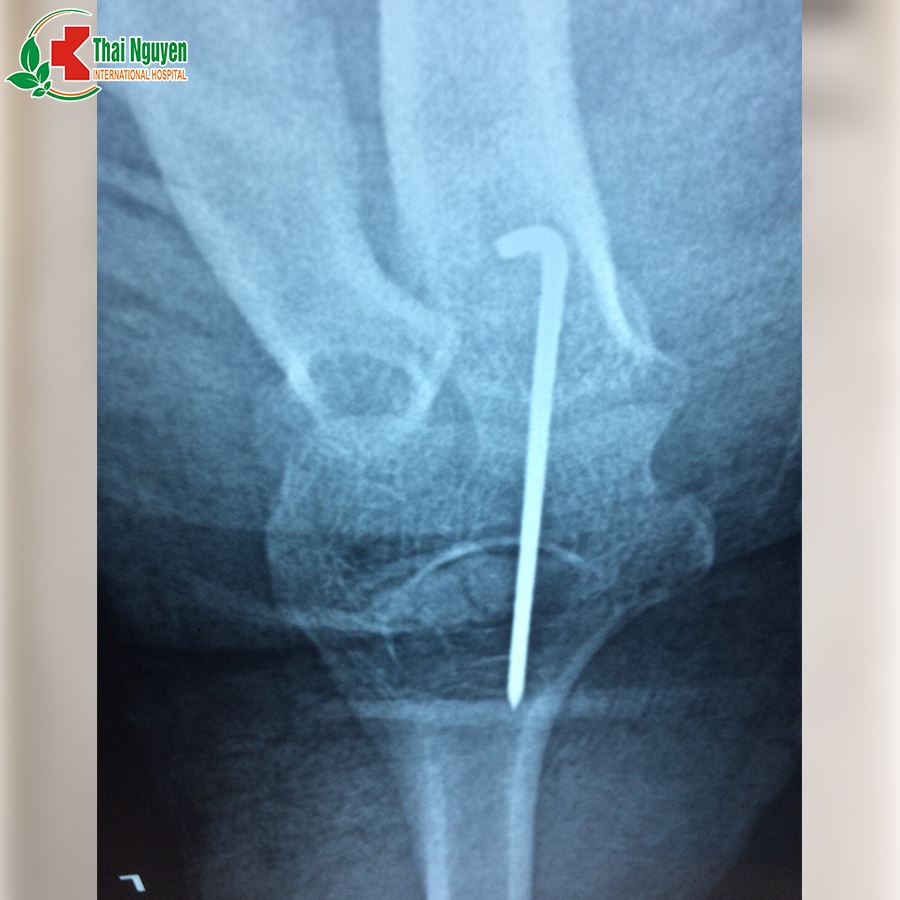

Ngày 01/03/2019, bệnh nhân Ngọc Thị Hoa, 41 tuổi, khuỷu tay trái bị sưng nề, khó cử động, sau khi đắp thuốc nam 1 tháng không có hiệu quả, bệnh nhân đã đến BVQT Thái Nguyên khám và điều trị. Sau khi thăm khám, chụp X-quang đã phát hiện bị trật khớp khuỷu tay trái.?? BSCK2 Lê Văn Bằng đã chỉ định phẫu thuật đặt lại khớp cho bệnh nhân do trật khớp đã lâu có biến chứng. Ca phẫu thuật thành công và hiện tại bệnh nhân đang trong quá trình hồi phục.